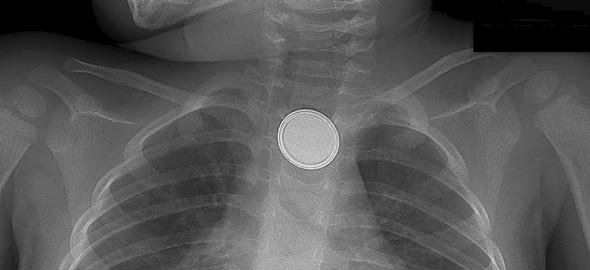

Το απλό καθημερινό αντικείμενο που στέρησε τη ζωή ενός παιδιού